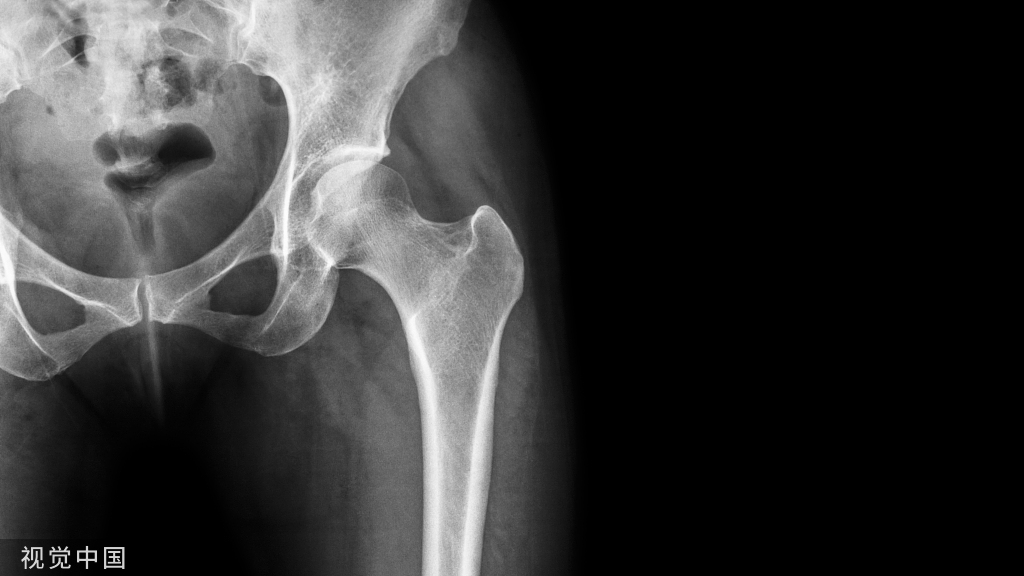

腰椎滑脱症

常见分类:一侧或两侧椎弓根峡部崩裂、不连续,患椎向前滑移,称为腰椎滑脱,又称真性滑脱;无峡部崩裂,而是因间盘退变或其他原因致椎间位置滑移,称为假性滑脱,又称退行性性滑脱。